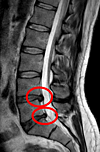

Une sciatique = hernie discale

Hernie discale sur les lombaires L4 L5

Miguel Tremblay, CC0, via Wikimedia Commons

Il est vrai qu'une hernie discale fait partie des causes principales de sciatique. On parle dans ce cas précis lombosciatique d'origine discogène.

Cependant, c'est loin d'être la seule cause.

La sciatique peut venir d'autres causes d'origine lombaire comme le rétrécissement du canal lombaire par arthrose ou par antérolysthésis.

Elle peut également venir d'une compression radiculaire sur le trajet du nerf. On ne parle plus dans ce cas de lombosciatique. Des affections tumorales peuvent en être la cause ou tout simplement une tension musculaire comme le syndrome du piriformis...

Il existe de nombreuses causes probables face à une sciatique. La sciatique n'est donc pas toujours causée par une hernie discale.